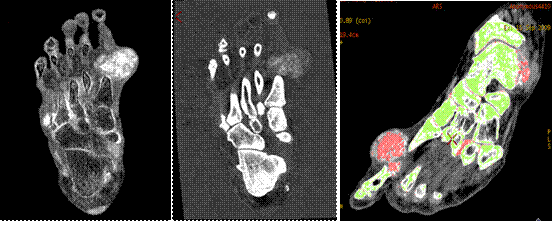

MD尿酸像 MD鈣基像 尿酸與骨質(zhì)分離

痛風(fēng)由于尿酸結(jié)晶體沉積在人體組織所致,而假性痛風(fēng)是由于磷酸鈣鹽沉積所致。如果在關(guān)節(jié)內(nèi)不進(jìn)行穿刺活檢無法評估尿酸結(jié)晶存在。寶石能譜CT物質(zhì)分離像可以提示痛風(fēng)或者假性痛風(fēng)存在,并加以鑒別。